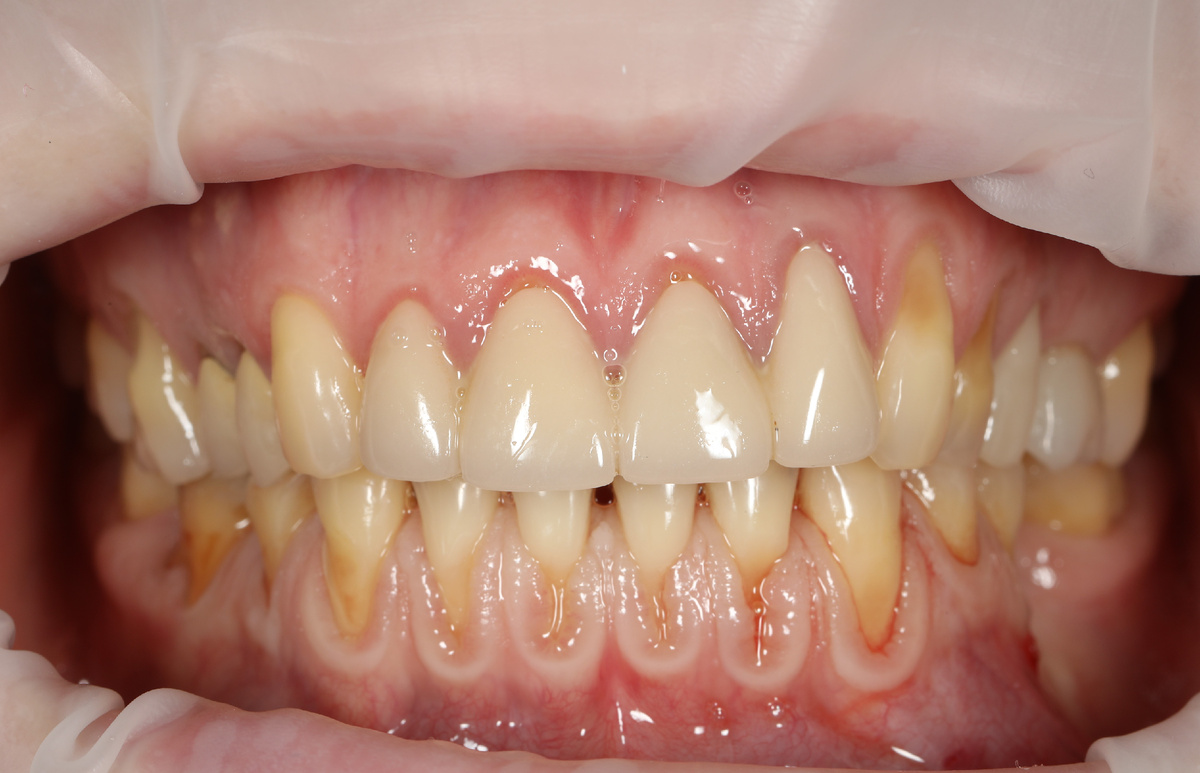

Рецессия дёсен — это состояние, при котором край десны смещается вниз (на нижней челюсти — вверх), оголяя корень зуба. Визуально зуб кажется «длиннее», а в зоне оголения часто появляется чувствительность к холодному, горячему или кислому.

Выглядит этот вот так:

рецессия на нижней челюсти и на некоторых зубах верхней челюсти

На нижней челюсти хорошо видны оголенные корни зубов – это и есть рецессия. Она почти никогда не возникает внезапно - это результат длительного воздействия на десну.